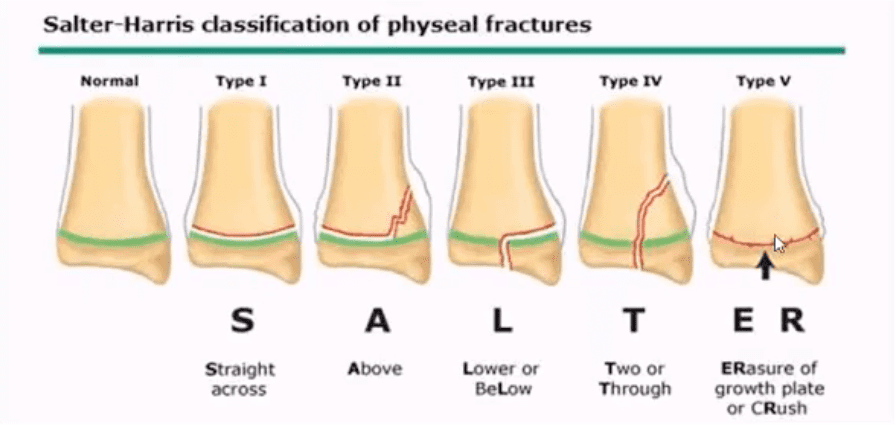

Pediatric Growth Plate Injuries

- Salter-Harris classification helps to diagnose and prognosticate physeal injuries.

- Helpful mnemonic: SALTR

- S: type 1-slip through growth plate

- A: type 2-above, Fx extends into metaphysis

- L: type 3-lower, intra-articular Fx extends through the epiphysis

- T: type4, “through” Fx extends through all: physis, metapysis and epiphysis.

- R: type 5, “ruined.” Crush injury to physis leading to complete death of teh growth plate

- Type 1 and 5: present with no fracture

- Type 2: has the best prognosis and considered the most common.

- Management: referral to pediatric orthopedic surgeon

- Complications: early physis closure, limb shortening, premature OA and others.